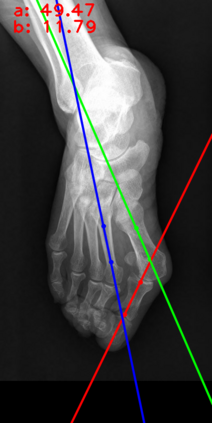

Angular measurements is essential to make a resonable treatment for Hallux valgus (HV), a common forefoot deformity. However, it still depends on manual labeling and measurement, which is time-consuming and sometimes unreliable. Automating this process is a thing of concern. However, it lack of dataset and the keypoints based method which made a great success in pose estimation is not suitable for this field.To solve the problems, we made a dataset and developed an algorithm based on deep learning and linear regression. It shows great fitting ability to the ground truth.